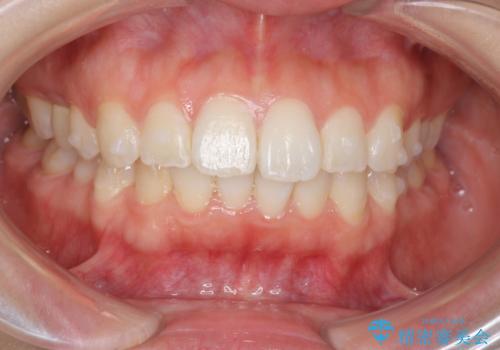

前歯のがたつき インビザラインで

- 前歯のがたつきを治したいとのことでした。歯を抜かずにできる範囲で引っ込めたいとのことでした。

歯を抜いているわけではないので、口元はそこまで変化はありませんが、前に出すことなくデコボコは取れたと思います。